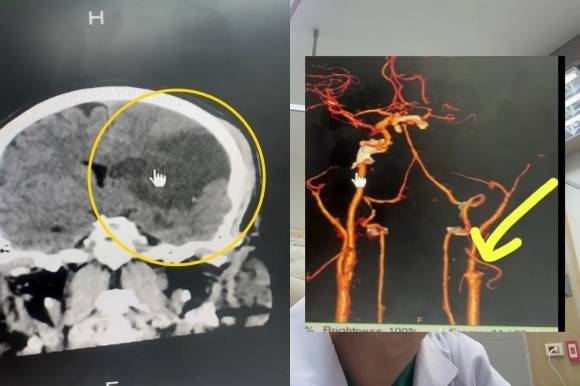

병원 검진 결과, 왼쪽 뇌의 상당 부분이 괴사한 것으로 밝혀졌다. 경동맥 박리 때문이었다. 이는 경동맥 혈관 내부 파열로 혈관벽이 찢어져 발생하는 질환이다.

경동맥은 심장에서 나온 피를 뇌로 보내 뇌가 원활하게 기능할 수 있도록 하는 혈관이다. 강한 마사지로 인해 경동맥이 손상되면 남성처럼 뇌졸중에 걸릴 수 있다.

프랏차 박사는 “환자의 뇌가 8시간 이상 피를 공급받지 못한 것으로 추정된다”며 “교육을 받지 않은 사람이 강하게 마사지를 하는 것은 매우 위험하다”고 지적했다.